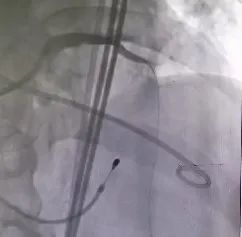

冠脉处理前

冠脉处理后

冠脉处理前后对比